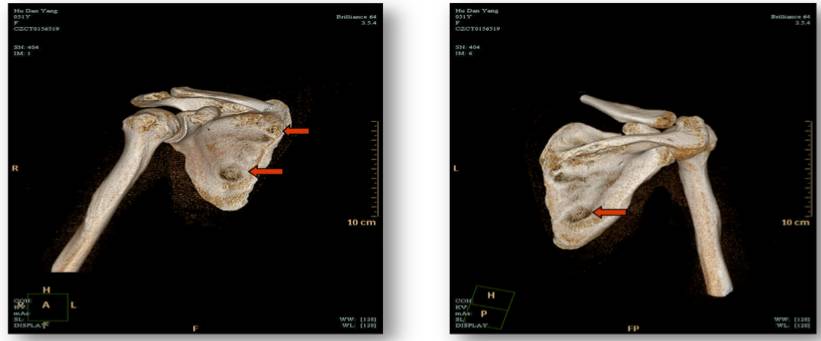

图一:2016-11-19 肩胛骨CT平扫+三维重建:右侧肩胛骨多发骨质破坏。

我们对胡女士的病情进行了MDT讨论,考虑到胡女士目前骨痛症状严重,并且辅助内分泌治疗不足两年,可能存在原发内分泌耐药的情况,讨论决定给予她NP方案及唑来膦酸的治疗。经历了4个周期的化疗,她的骨痛情况明显好转,恢复正常行走,肩胛骨CT平扫+三维重建提示右侧肩胛骨骨质破坏较前好转。但此时胡女士已无法耐受化疗的各种不良反应,提出停止化疗的要求。

图二:2017.3.8肩胛骨CT平扫+三维重建:右侧肩胛骨骨质破坏较前好转。